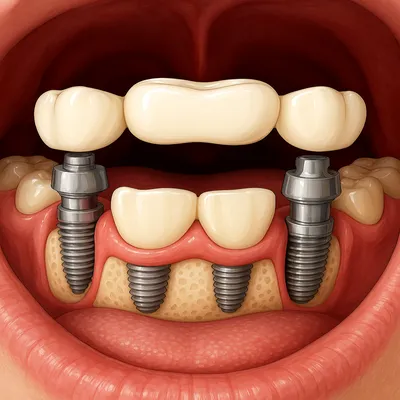

بریج ایمپلنتی (Implant-supported)

کِی؟ وقتی دندانِ پایه مناسب نداریم یا چند دندانِ کنارِ هم از دست رفتهاند.

ساختار: اتصالِ پروتز ثابت به ایمپلنتها؛ بدون تراشِ دندانهای سالم.

مزایا: حفظِ استخوان فک، طولعمر بالا، زیبایی و عملکرد عالی (بهویژه با زیرکونیا یا سرامیکهای پیشرفته).

معایب: نیاز به جراحی و زمانِ اُسواینترگریشن؛ هزینهی بالاتر.

نکتهی انتخاب: ایدهآل برای بیدندانیِ چنددندانی یا وقتی پایههای طبیعی ضعیفاند.

پروتز ثابت روی ایمپلنت با ظاهر طبیعی و استحکام بالا